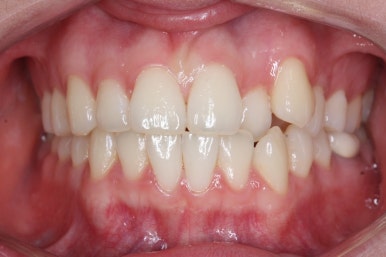

부산부정교합 키다리아저씨치과에 처음 내원하셨을 때의 입안 모습입니다.

위아래 앞니가 삐뚤고 특히 왼쪽 위 송곳니는 밖으로 두드러져 덧니 양상입니다. 윗니는 덧니쪽으로 쏠려 있어서 치열의 중앙이 맞지 않습니다.

전반적인 삐뚤어진 양, 돌출의 느낌, 골격의 비율 등을 고려했을 때 발치 없이 치료를 하기로 했습니다.